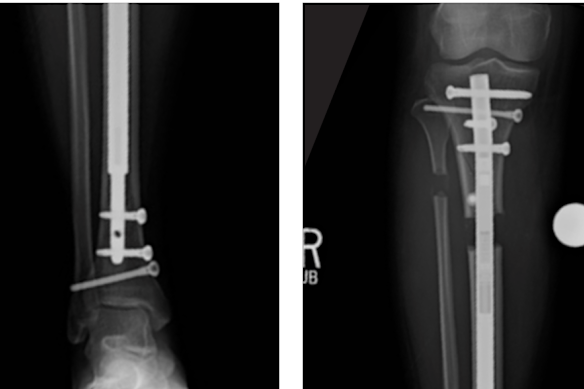

Surgical nails have been an alternative to the Ilizarov method since the 1990s where large nails are inserted into the bone and external remote controls or magnets move the nail externally to cause fractures, eliminating the metal cage and associated infection risks.

Paley invented the Stryde Nail with manufacturer Nuvasive in 2018, which used stainless steel instead of titanium, allowing heavier patients to weight-bear immediately after surgery.

Promotional material depicting the use of the Stryde nail developed by Dror Paley.

She would end up suing Nuvasive for negligence, alleging the device generated chromium toxicity or heavy-metal poisoning which caused these injuries before it was recalled. US court documents in that case allege X-rays discovered “leftover fragments around the implantation site and surrounding tissues”.